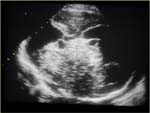

Echographiquement : Aspect multicloisonné de la masse

Apparence modifiée par une hémorragie intra-kystique

Absence de vascularisation au Doppler

Echographiquement : Masse multicloisonnée (cloisons solides sans vascularisation)

Œdème des parties molles